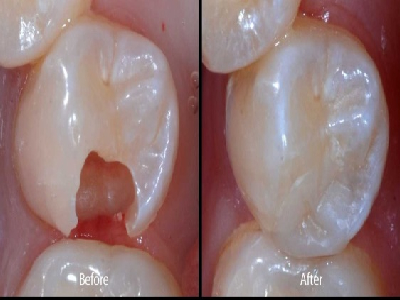

We provide a wide range of dental services which includes Oral Prophylaxis, Tooth Extraction, Tooth Fillings, Veneers, Complete and partial dentures, Crowns, Fixed Bridges, Braces, Retainers, Periodontal/Gum Treatment, Root Canal Treatment, Bleaching/Teeth Whitening, Cosmetic Dentistry, Minor Oral Surgical procedures, and Paediatric Dentistry.